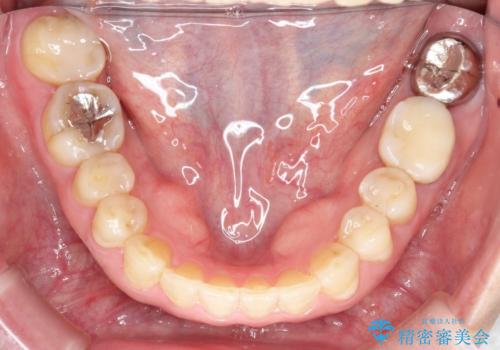

- 前歯のガタガタを主訴に来院されました。

上の歯の前突も気になってたため、奥歯の遠心移動も行いながらインビザラインにて治療を行いました。

前歯も下がり満足していただきました。

今回は奥歯の遠心移動とIPRを行って配列しています。